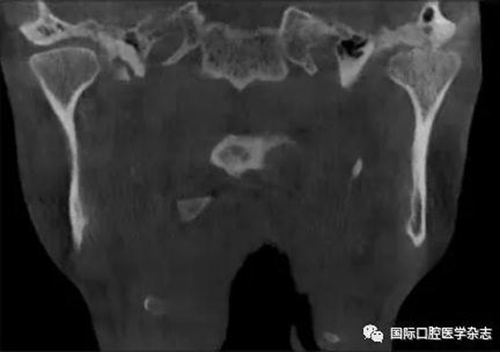

(3)骨關(guān)節(jié)?。▓D2):屬于顳下頜關(guān)節(jié)器質(zhì)性改變,主要發(fā)生在髁突的骨質(zhì)變化,其次是關(guān)節(jié)窩及關(guān)節(jié)結(jié)節(jié)的改變。影像學(xué)檢查發(fā)現(xiàn)骨、軟骨和關(guān)節(jié)盤有退行性改變,關(guān)節(jié)運(yùn)動(dòng)時(shí)可聞及連續(xù)摩擦音。伴有滑膜炎或關(guān)節(jié)囊炎時(shí),有開口痛和咀嚼痛,開口受限,這時(shí)可稱骨關(guān)節(jié)炎。

圖 2 骨關(guān)節(jié)病